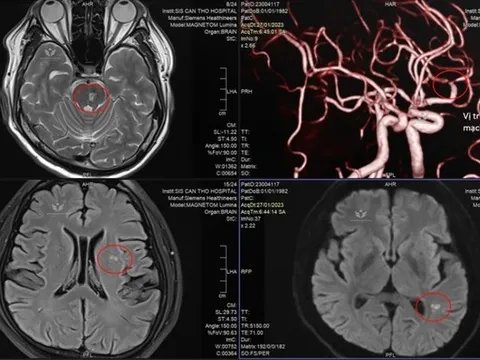

Doanh nhân trẻ đột quỵ vì thường xuyên tiếp đối tác bằng rượu bia

Nam doanh nhân 41 tuổi, đến bệnh viện trong tình trạng tê yếu nửa người do nhồi máu não. Khai thác bệnh sử của bác sĩ từ phía người bệnh ghi nhận, trước đó doanh nhân trẻ thường xuyên tiếp đối tác bằng rượu bia.